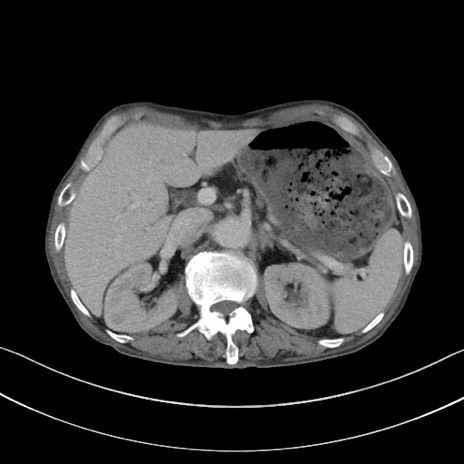

症例3(横断像)

【症例】 70歳代男性

【主訴】右鼠径部腫瘤、疼痛

【現病歴】本日朝より上記主訴あり、受診。

【既往歴】膀胱癌にて膀胱全摘、両側尿管皮膚瘻

【データ】WBC 5600、CRP 0.56